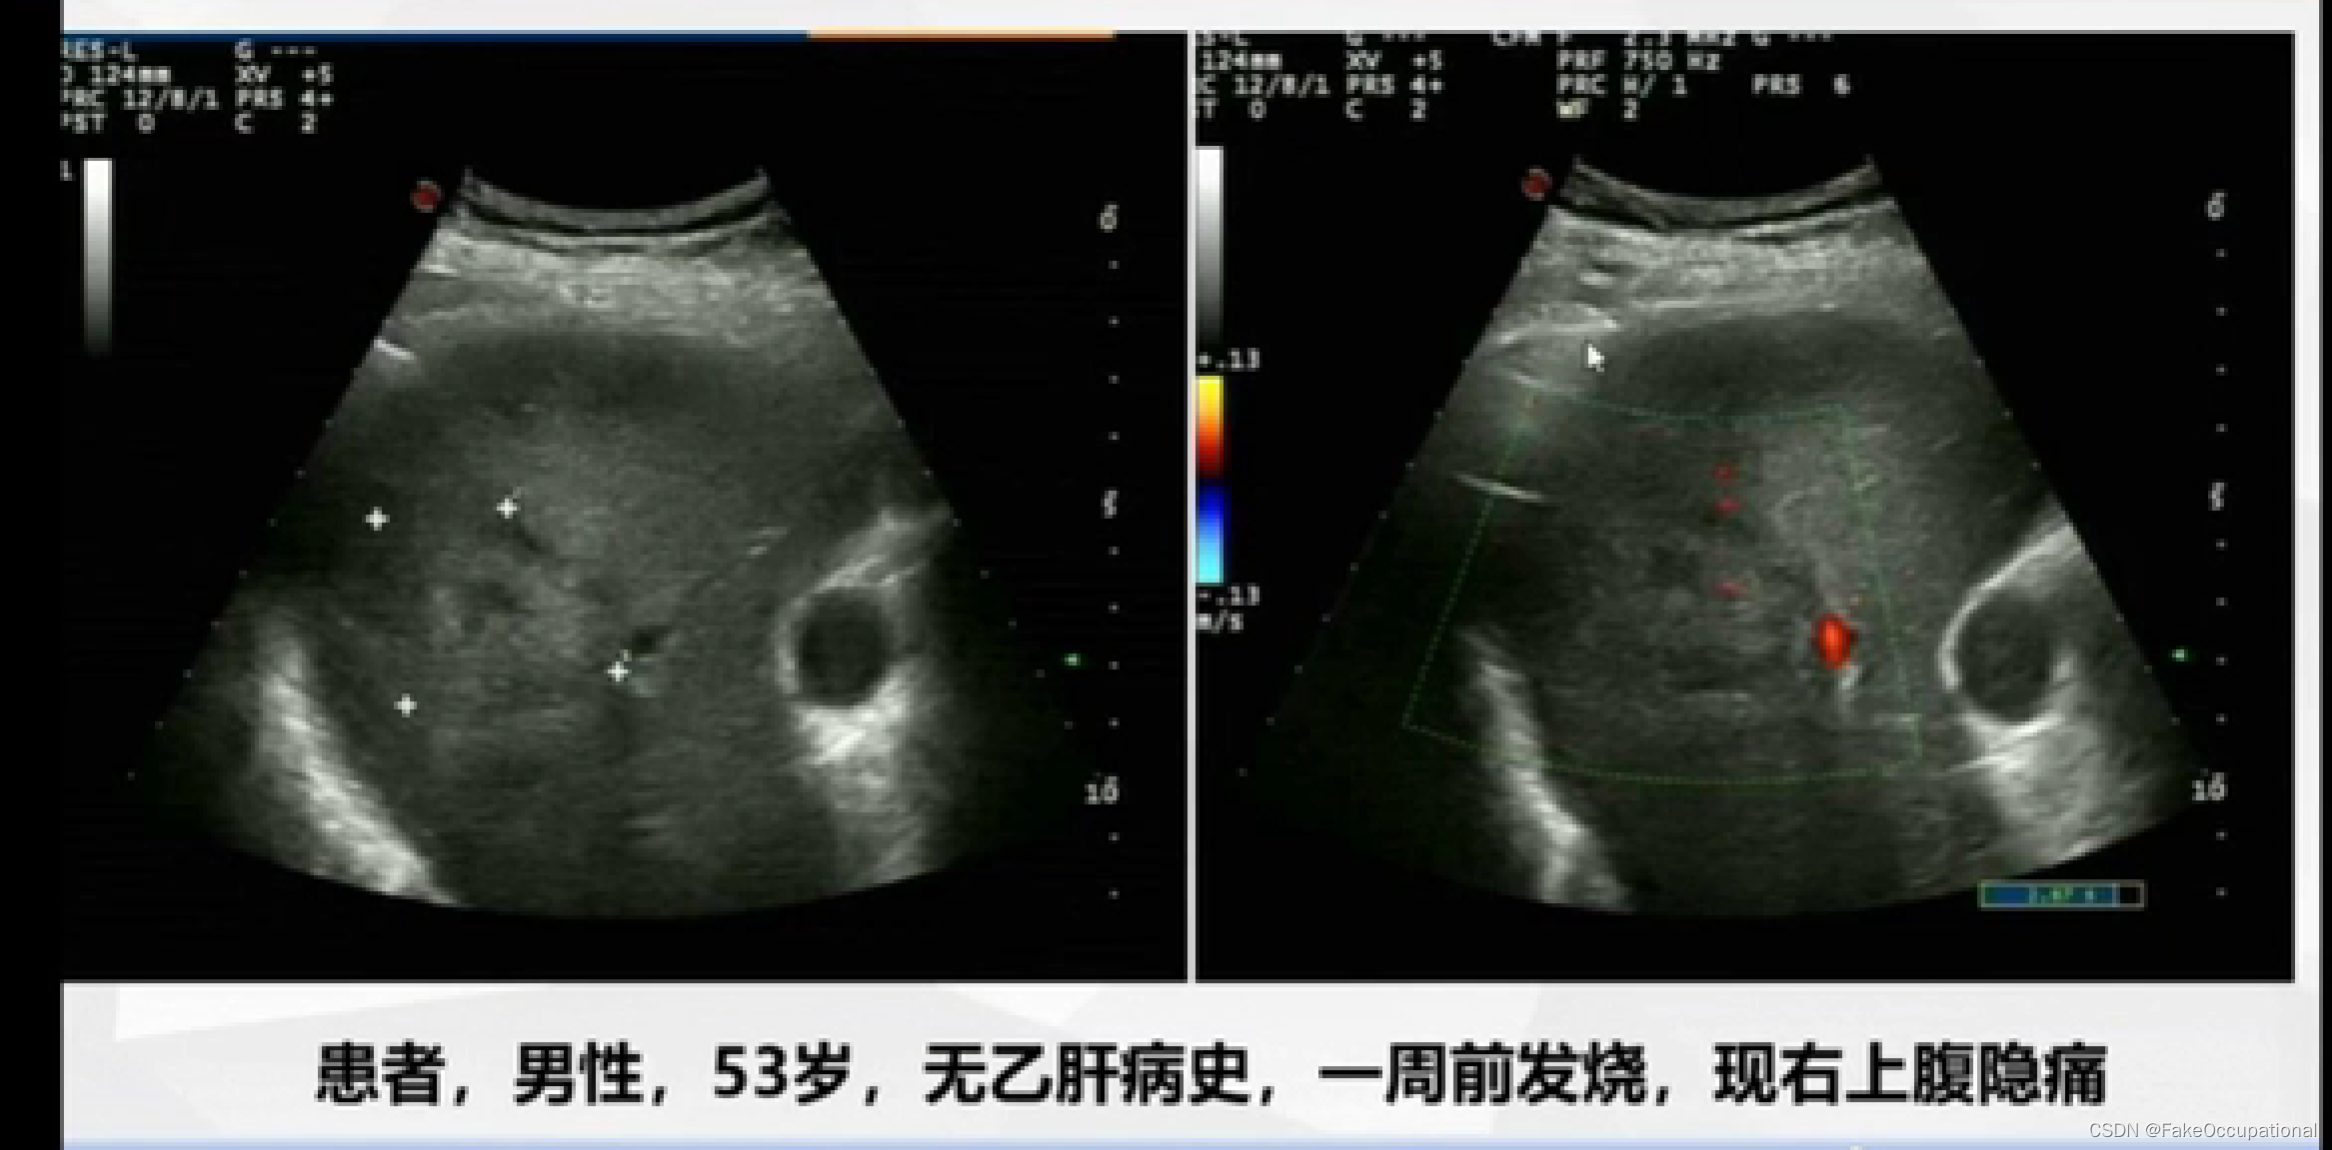

异常肝脏超声表现